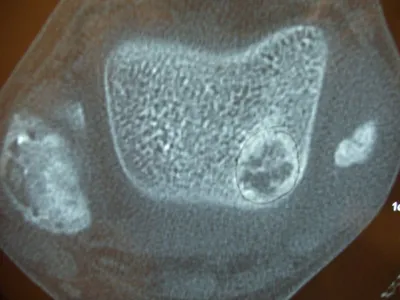

A series of intraop ankle arthroscopy pics of synovial chondromatosis with OCD talus and tibia and microfracture.

Pic of an OCD in the talar dome due to pressure from the nodule.